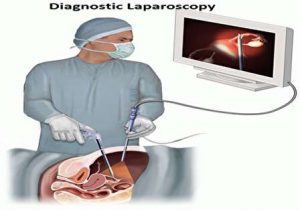

عمل لاپاراسکوپی چیست و چگونه انجام میشود؟

6 دقیقه